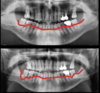

Dominique, 58 ans, présente une parodontale avec des saignements et mobilités dentaires.

Suite à un traitement non chirurgical en 5 séances, une chirurgie a été réalisée pour traiter les lésions profondes résiduelles et combler ses lésions infra-osseuses par des cellules souches et de l'os.

A 10 mois post opératoire, nous observons un comblement total des lésions infra-osseuses, la disparition des l&sions profondes et une architecture osseuse horizontale.

La patiente est désormais en santé parodontale et ses dents peuvent être conservées.